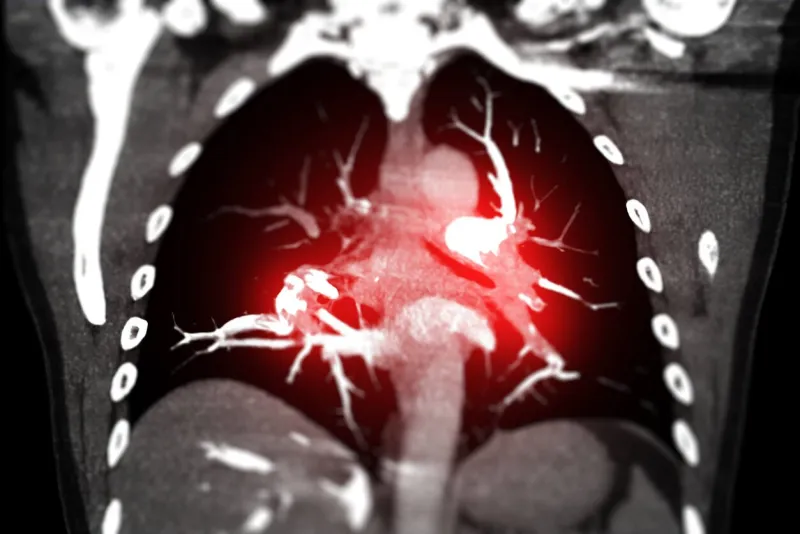

cta chest or ctpa with contrast media coronal view showing pulmonary embolism (pe)

Istock

En juin dernier, l’hôpital de Châteaudun en Eure-et-Loire a été condamné pour avoir diagnostiqué une crise d’asthme sévère à une jeune patiente, malheureusement décédée quelques jours plus tard d’une embolie pulmonaire. Des cas similaires sont rapportés dans les pages de Faits Divers plus ou moins régulièrement. De fait, cette maladie peut être confondue avec d’autres maladies et ses symptômes (gêne respiratoire, angoisse, douleur thoracique…) ne sont pas toujours spécifiques.